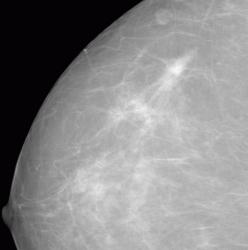

СЛУЧАЙ РЫБАКОВОЙ Л. А. "Инфильтрирующий рак правой молочной железы".

"Инфильтрирующий рак правой молочной железы".

Уважаемая Людмила Александровна, а как вы расцениваете участки, отмеченые желтыми стрелками? нет ли здесь мультицентричного рака?

Каюсь, вина моя. Людмила Александровна указала, что имеется "мультифокальный рост".